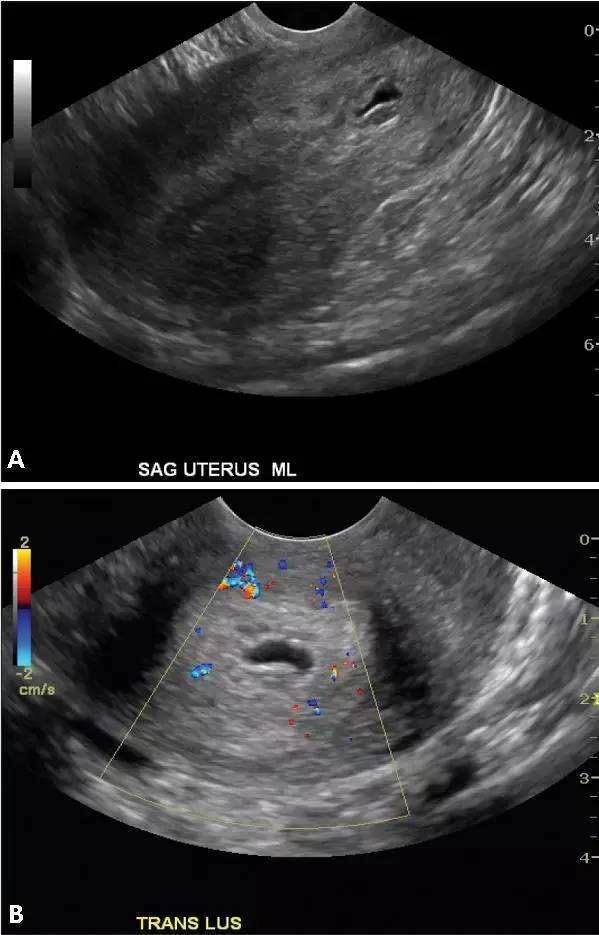

圖 1 腹腔異位妊娠。A,經腹部超聲矢狀面圖像顯示位于子宮(U)上方、卵巢(O)前方的腹腔妊娠。實時超聲檢查時可見胎兒活動;B,經腹部超聲橫切面圖像顯示另一更大孕周的腹腔妊娠,同樣位于子宮上方